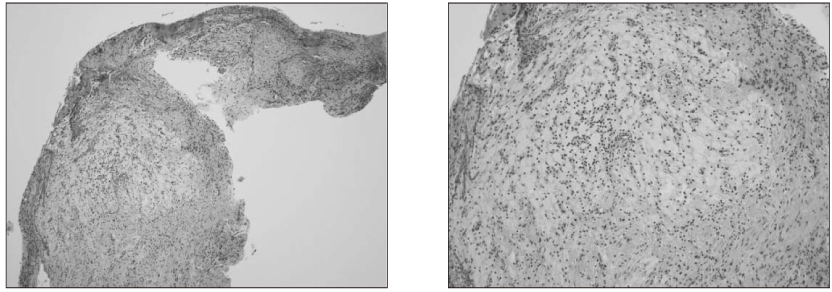

Figure 9

Histological appearance of surgically removed tissue.

jkacd-31-161-g009.jpg

Figure 9 Histological appearance of surgically removed tissue.